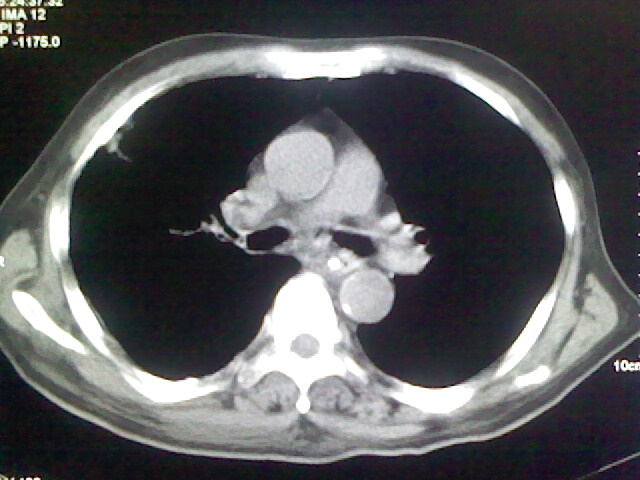

男,70岁,脑出血,长期卧床,左侧背部可触及肿块

右侧肺部见片状密度增高影,边缘模糊。考虑炎症。另食管壁增厚。

右肺上叶前段病呈楔形,其尖端指向肺门,考虑肺动脉栓塞可能性大.

食道里是什么

你放上去的